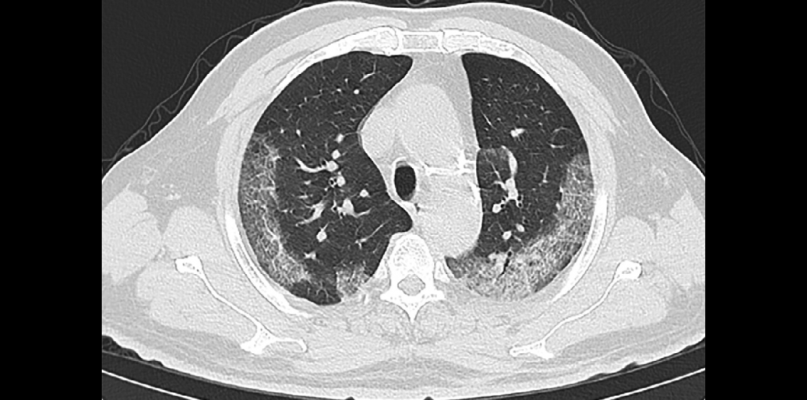

Examples of typical chest CT findings compatible with COVID-19 pneumonia in patients with epidemiological and clinical presentation suspicious for COVID-19 infection. This image is part of the original research, Sensitivity of Chest CT for COVID-19: Comparison to RT-PCR, published Feb. 19, 2020, in Radiology Online.

Although RT-PCR has been the standard of reference in diagnosing COVID-19, in this series of 51 patients with chest CT and RT-PCR assay performed within 3 days, the sensitivity of CT for COVID-19 infection was 98% compared to RT-PCR sensitivity of 71 percent.

“In our series, the sensitivity of chest CT was greater than that of RT-PCR. Our results support the use of chest CT for screening for COVD-19 for patients with clinical and epidemiologic features compatible with COVID-19 infection particularly when RT-PCR testing is negative,” the authors wrote.